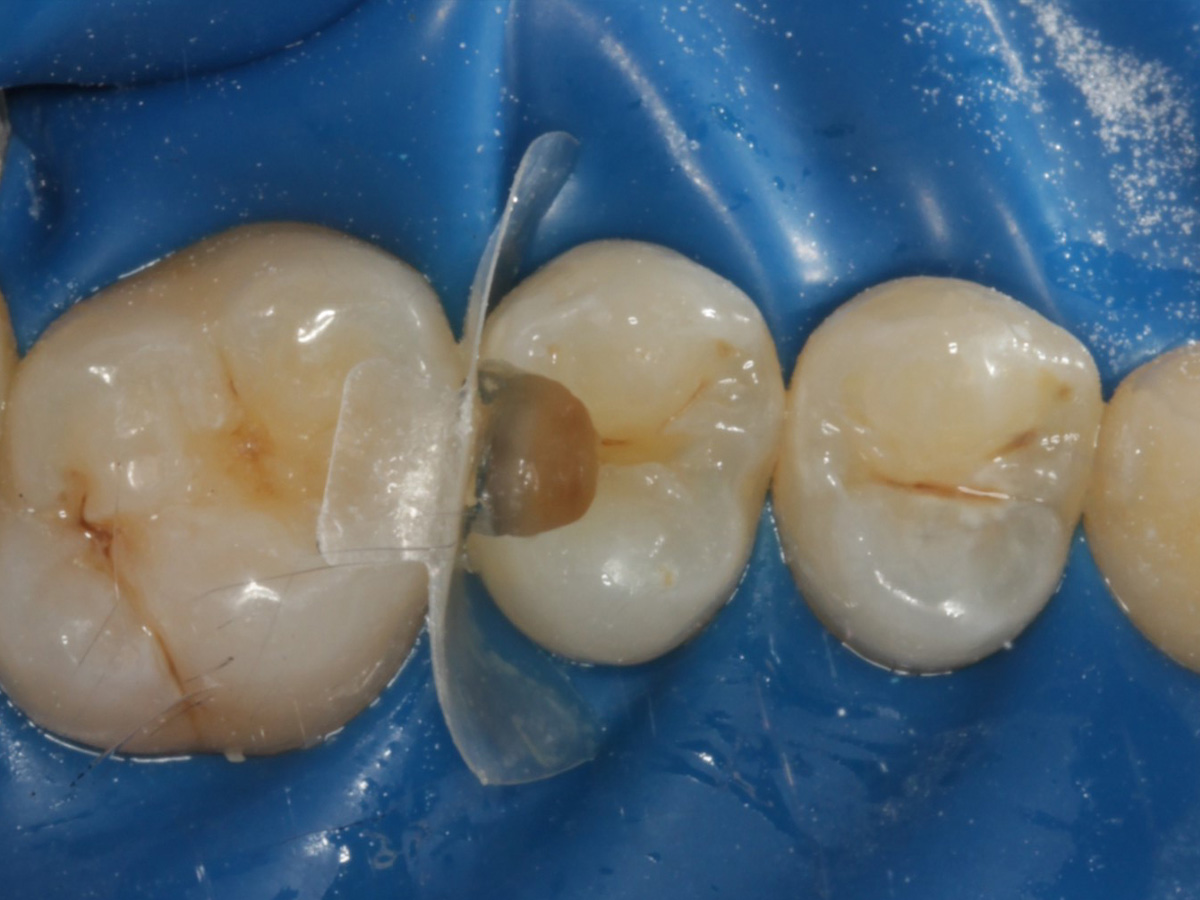

Abbildung 8

Nach Anschrägung der Schmelzränder und Reinigung der Kavitätenränder mit diamantierter Hubfeile